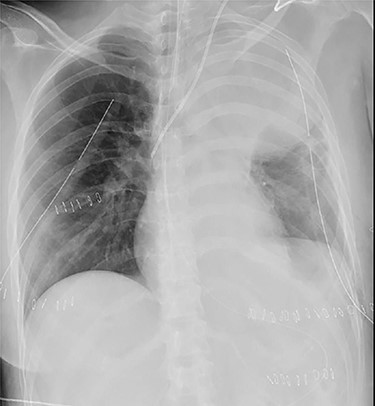

A 38-year-old woman with schizophrenia committed suicide by a self-infliction of sharp force into the chest and abdomen. She presented to our hospital in a critical condition. On arrival in the emergency room (ER), she developed hemorrhagic shock, which leads to an emergent abdominal damage control surgery under general anesthesia. She lost cardiac activity in the operating room during exploratory laparotomy. A left-sided basal thoracostomy, cross-clamping of the descending thoracic aorta, and open cardiac massage were also performed. She received gauze packing at the bleeding point and temporarily close the abdomen and chest wall. After the surgery, she was transferred to the intensive care unit with mechanical ventilation and recovered from hemorrhagic shock. Two days later, a second-look laparotomy was performed. ER doctors verified the hemostasis and closed the patient’s abdomen and chest. On the same day, a chest radiograph revealed pulmonary atelectasis of the left upper lobe (Fig. 1). Computed tomography (CT) revealed alveolar bleeding, pneumonia and atelectasis of the left upper lobe (Fig. 2). Despite antibiotic therapy and repeated endobronchial sputum aspiration, radiologic findings were not improved. On the seventh postoperative day, she was referred to our department for suspected lung abscess. When compared to the chest CT images on the day of initial surgery, pulmonary torsion was suggested (Fig. 3A). The sagittal CT images were reconstructed, and the torsion of the left upper lung lobe was diagnosed (Fig. 3B). Therefore, an emergency left upper lobectomy was performed through a left thoracotomy. Intraoperatively, the left upper lung lobe was rotated clockwise and was hemorrhagically and congestive infarcted. Due to severe pulmonary congestion, it was difficult to obtain the surgical field of view. The pericardial sac was opened and the intrapericardial isolation of the left upper pulmonary vein was performed. To prevent separation of the thrombus and necrotic material in the left upper lobe, we first dissected the left upper pulmonary vein before resolving the torsion and performing the lobectomy. She had a complete pulmonary fissure. Moreover, only one first pulmonary artery branch had ruled the approximately pulmonary arterial flow of her left upper lobe. The left upper lobectomy was performed. The patient made an uneventful recovery.

Computed tomography images of 2 days after initial emergency operation.